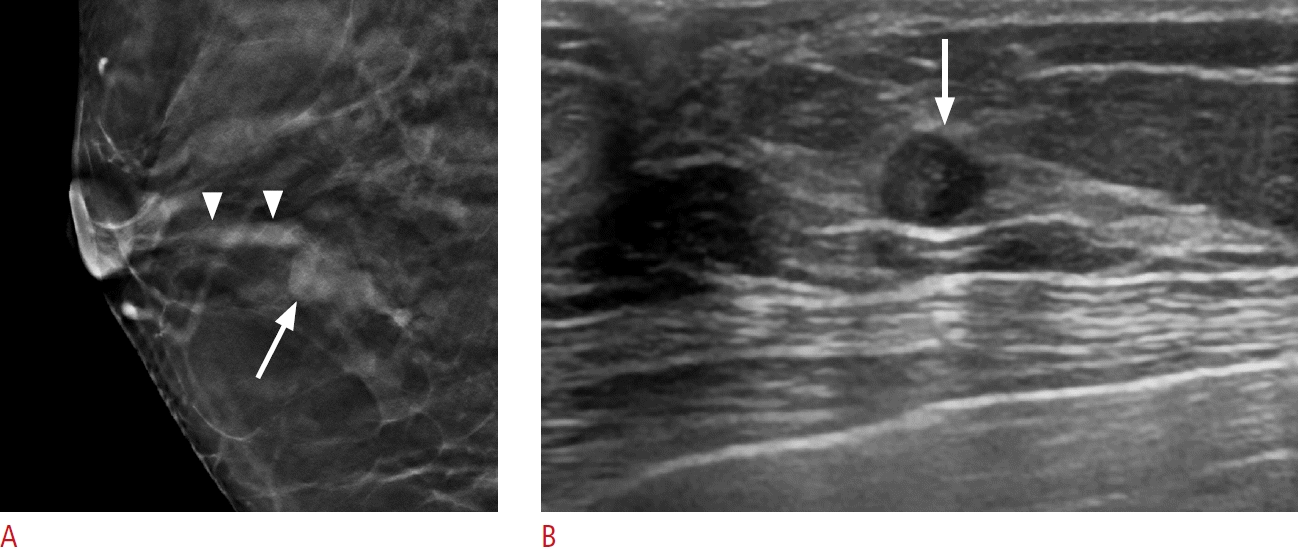

10. Ayres VJ, Ramalho LC, Fernandes CE, Fleury EFC, Pompei LM. Solitary dilated duct visualised by mammography: ultrasound and anatomopathological correlation. Clin Radiol. 2020; 75:962.

11. Choudhery S, Simmons C, Woodard GA, Bhatt AA, Anderson TL, Lee CU. Outcomes of solitary dilated breast ducts in symptomatic and asymptomatic patients. Br J Radiol. 2020; 93:20191039.

12. Panigrahi B, Fernandes K, Mullen LA, Oluyemi E, Myers KS, Philip M, et al. Solitary dilated ducts revisited: malignancy rate and implications for management. Acad Radiol. 2023; 30:807–813.

35. Ha SM, Choi WJ, Han BK, Kim HH, Moon WK, Kim MJ, et al. Assessment of nonmass lesions detected with screening breast US based on mammographic findings. Radiology. 2024; 313:e240043.